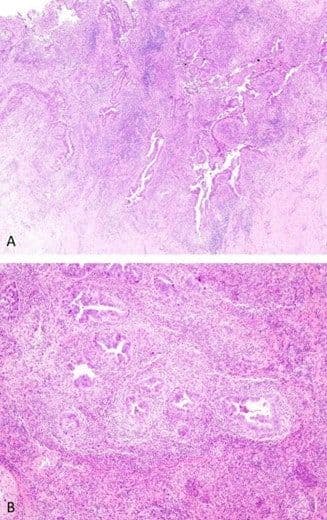

High-risk squamous intraepithelial lesion (HSIL) is associated with infection by high-risk HPV serotypes. HSIL typically presents as a flat lesion (Figure 6), but may also be exophytic, where the colposcopic and microscopic distinction from papillary squamous cell carcinoma (see below) may be challenging.

Figure 6

Histologically, HSIL is characterized by significant architectural disorder, cell crowding, and cytologic atypia in the basal layer. There is generally impaired (CIN 2) or no (CIN 3) maturation toward the epithelial surface, and mitoses are frequently conspicuous in the superficial epithelial layers. Microscopic involvement of endocervical crypts is common (Figure 7) and should be noted in the pathology report.

Figure 7